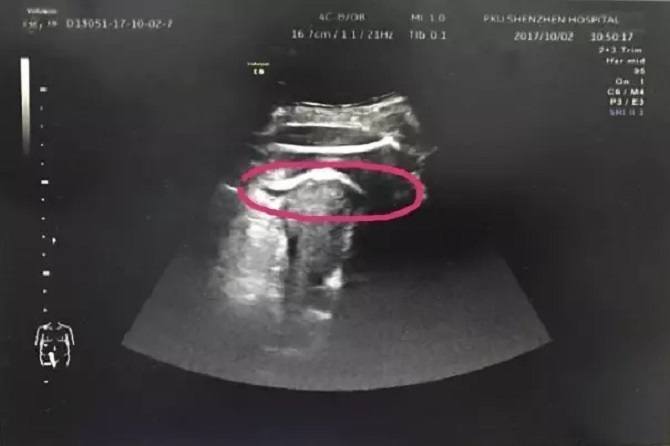

They suspected that the womb had ruptured, so they decided to perform an ultrasound to confirm. They were shocked by what they found.

The foetus’s leg had apparently, “kicked through” the uterus wall, into the mom’s abdominal cavity, and her thighs were stuck.

They found blood in the mom’s stomach, and a 7 cm tear in her womb wall.